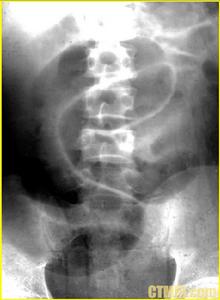

1.X線表現一般情況下立位腹平片可見擴張腸管內大量氣液平存在,臥位腹平片能觀察到擴張的結腸,如盲腸扭轉也可見小腸積氣擴張;但非閉襻性結腸扭轉由於只有一個梗阻點,所以往往與單純性結腸梗阻表現一樣,亦表現為梗阻以上結腸腸管的擴大,所以在透視或平片中一般難以鑑別,只有為了明確結腸梗阻的性質而行鋇灌腸檢查時,才能明確診斷。此時扭轉梗阻處可顯示螺鏇狀變細腸管或在變細腸管中見到扭曲交叉的黏膜(沿腸管縱軸),甚至見到鋇劑通過梗阻處進入近側腸管。閉襻性結腸扭轉典型的X線表現,即扭轉段腸襻在臥位腹平片上能顯示出擴大的閉襻就像充了氣的橢圓形氣球,特別是乙狀結腸扭轉其極度擴張的腸曲呈咖啡豆狀,中間可見雙線條狀腸壁影,由於腸壁變薄,兩側緣表現為圓結狀緻密增白影,擴大的腔內皺襞消失。鋇灌腸檢查閉襻性乙狀結腸扭轉,會見到結腸扭轉處顯示鳥嘴狀狹窄,加壓多次灌鋇此徵象均存在且鋇劑不能通過此狹窄處。橫結腸扭轉擴張腸曲於中上腹呈橢圓形擴張,中間也可見雙線條狀腸壁影,降結腸萎陷。盲腸扭轉多為順時針方向,除了盲腸呈圓形擴張外,小腸也擴張明顯。